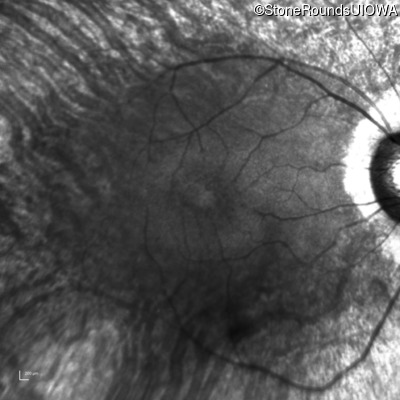

Age at visit: 49 years (Visit 2)